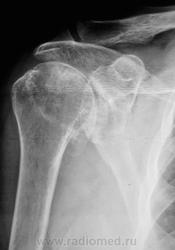

Смущает дополнительный "контур" по стрелкам.

Думаю,что это "неодокостеневшие" костные разрастания(не знаю,как точно обозвать).

Что в анамнезе? Была травма? После чего боли появились. Что можно сказать об объёме движений? Мне кажется, что изменения связаны с обызвествлением суставной сумки.

Мне кажется, что изменения связаны с обызвествлением суставной сумки.

Мне тоже так показалось.

Для оценки состояния хрящевой губы МРТ

А может быть для начала УЗИ? Пока она до МРТ доедет. Есть такое понятие "замороженное плечо". Возможно оно, вот узнать бы объём движений.

Вот, вот, пациентка так и говорит, что как бы плечо замерзло. Объём движений пациентной оценивается, как нормальный, но боли мешают...